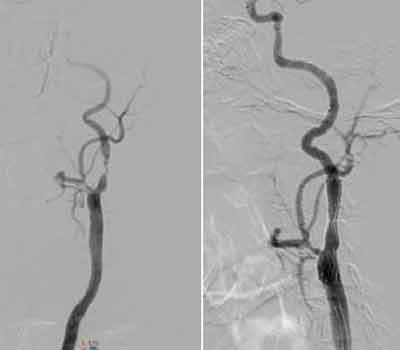

Bệnh nhân Nguyễn Thanh P. (74 tuổi) có tiền sử bị cao huyết áp và tai biến mạch máu não nhưng không để lại di chứng yếu liệt nửa người. Bệnh nhân vào khoa Nội bệnh viện Hữu nghị vì đau đầu, chóng mặt và thoáng ngất. Sau đó đã được chụp phim cắt lớp vi tính đa dãy đầu dò có hình ảnh xơ vữa gây hẹp rất nặng một nhánh động mạch cảnh bên trái làm hạn chế dòng máu chảy lên não.

Mảng xơ vữa rất lớn này có thể bị bong ra bất kỳ lúc nào khi bệnh nhân có cơn huyết áp tăng cao, làm nghẽn hoàn toàn dòng máu lên não gây nên cơn nhồi máu não khiến bệnh nhân hôn mê, liệt hoàn toàn nửa người và có thể tử vong.

![]() |

| Hình chụp MSCT 64 hẹp rất nặng động mạch cảnh trong trái. |

Chính vì vậy các bác sĩ khoa Nội đã tiến hành hội chẩn gấp với các bác sĩ khoa Tim mạch can thiệp và đưa ra quyết định can thiệp đặt stent khai thông dòng chảy động mạch cảnh. Bệnh nhân đã được can thiệp thành công và xuất viện sau 10 ngày. Bệnh nhân phải được uống thuốc chống đông máu lâu dài để đề phòng nguy cơ tắc mạch tái phát.

| Hình ảnh chụp mạch máu động mạch cảnh hẹp nặng trước và kết quả sau đặt stent động mạch cảnh. |